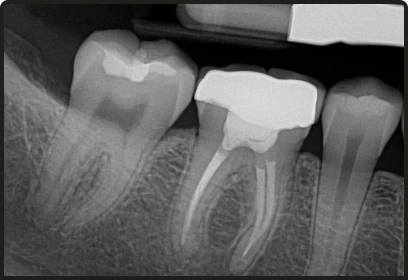

- We utilize digital imaging and rotary endodontics to provide more precise results and faster recovery times.

Root Canal Therapy with Dental Crown

The complete restoration package.

- High-quality zirconia or E-max crown for natural aesthetics.

- Comprehensive protection against future fractures or reinfection.

Why do I need a crown after a root canal?

A root canal removes the tooth's blood supply, making it brittle. A crown protects it from fracturing under biting pressure.